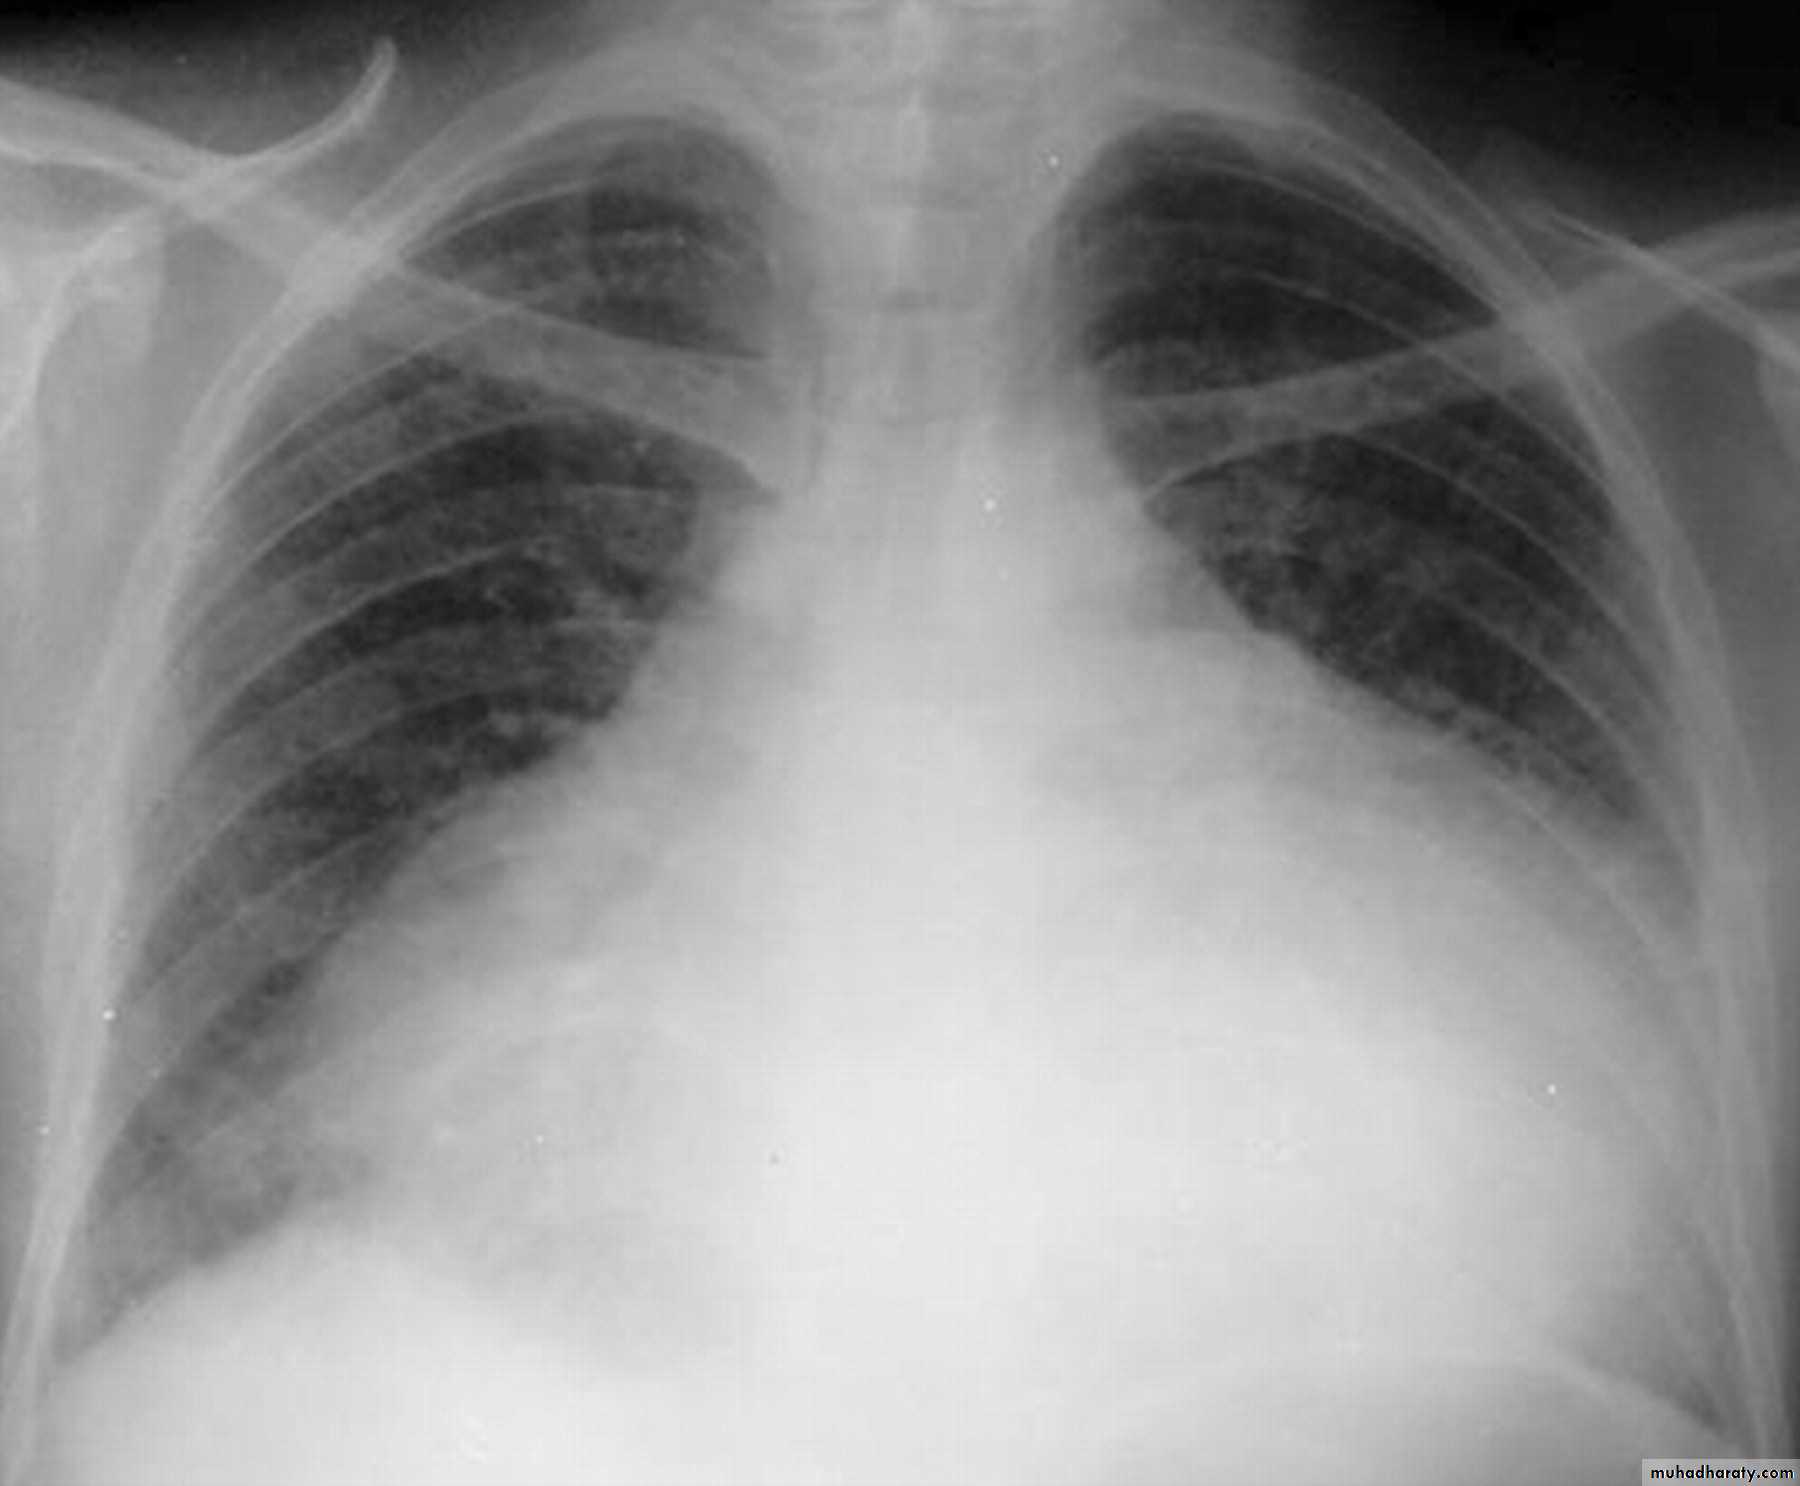

Congestive cardiac failure (CCF) is a form of cardiac failure which is primarily manifested by the heart inability to pump the volume of blood. It can affect the left (common) or right cardiac chambers or both.

Radiographic features

Chest radiograph

With left sided congestive cardiac failure, the features are that of pulmonary edema which includes:

central pulmonary venous congestion ( prominent hilum )

cephalisation of pulmonary veins ( upper lobe pulmonary venous diversion )

(Septal lines) pulmonary interstitial oedema

pulmonary alveolar oedema

Cardiomegaly

Pleural effusion